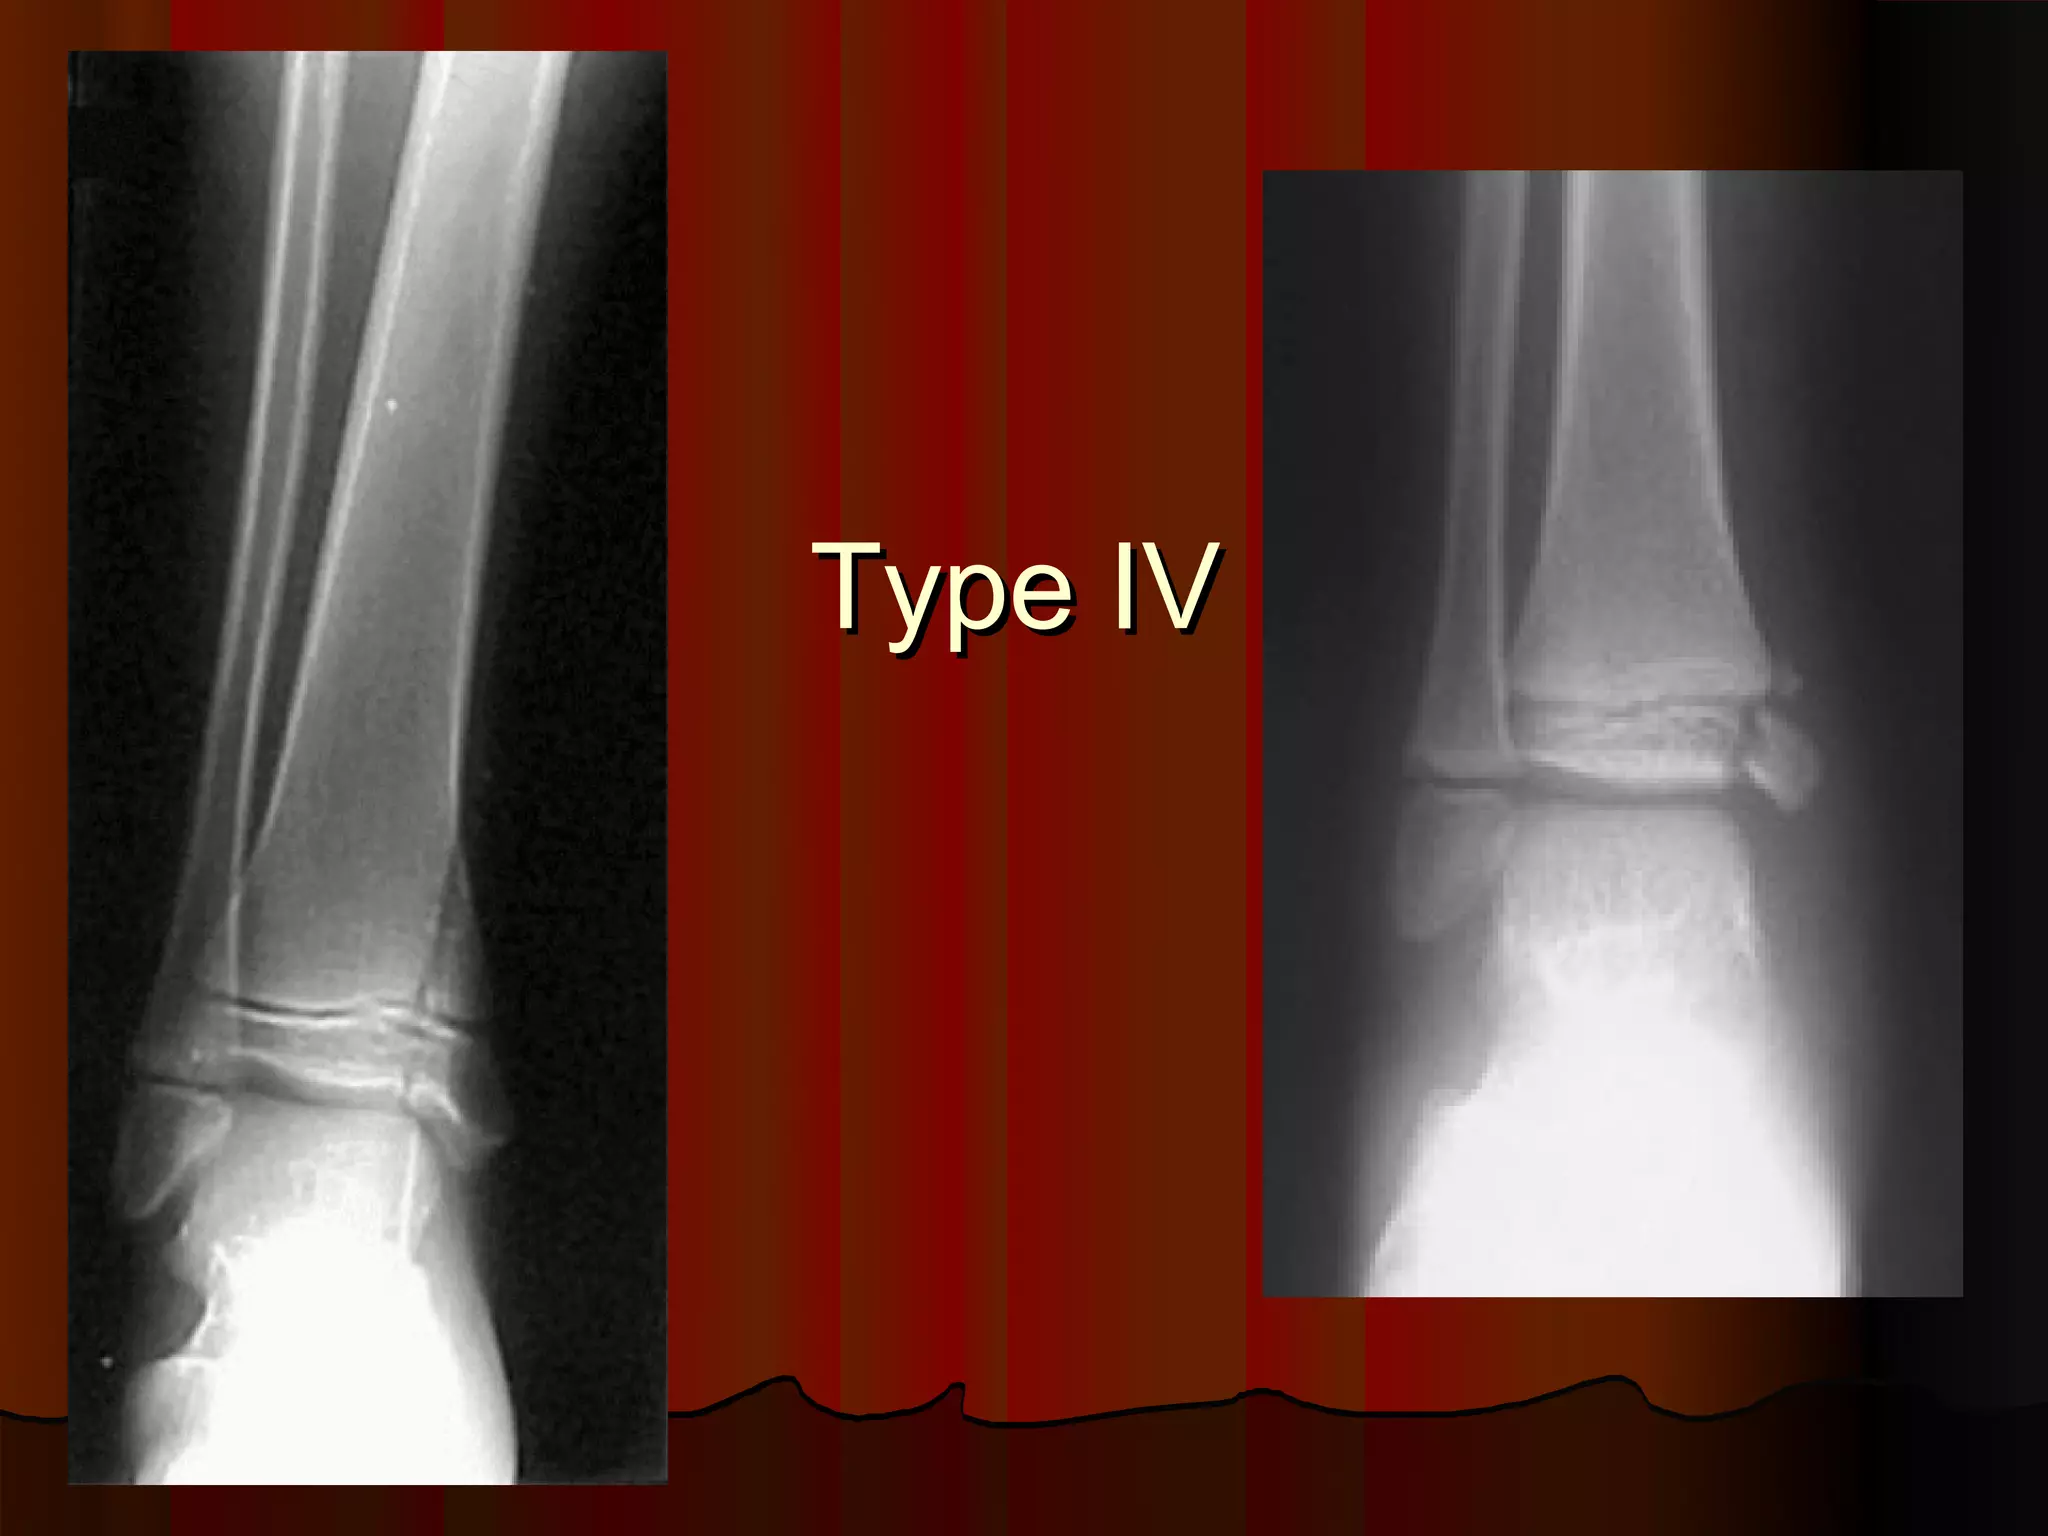

Description of Salter-Harris Type IV injury.